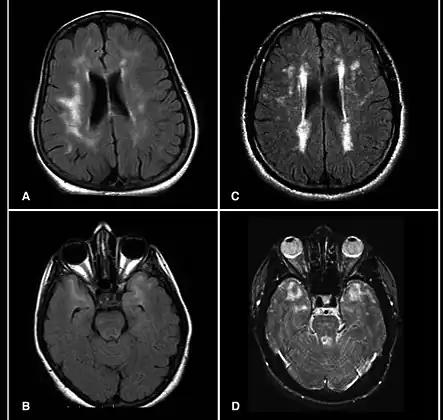

| Brain MRI from patients with CADASIL showing multiple lesions. | |

MRIs show hypointensities on T1-weighted images and hyperintensities on T2-weighted images, usually multiple confluent white matter lesions of various sizes, are characteristic. These lesions are concentrated around the basal ganglia, peri-ventricular white matter, and the pons, and are similar to those seen in Binswanger disease.[2][13]

These white matter lesions are also seen in asymptomatic individuals with the mutated gene.[14]

While MRI is not used to diagnose CADASIL, it can show the progression of white matter changes even decades before onset of symptoms.